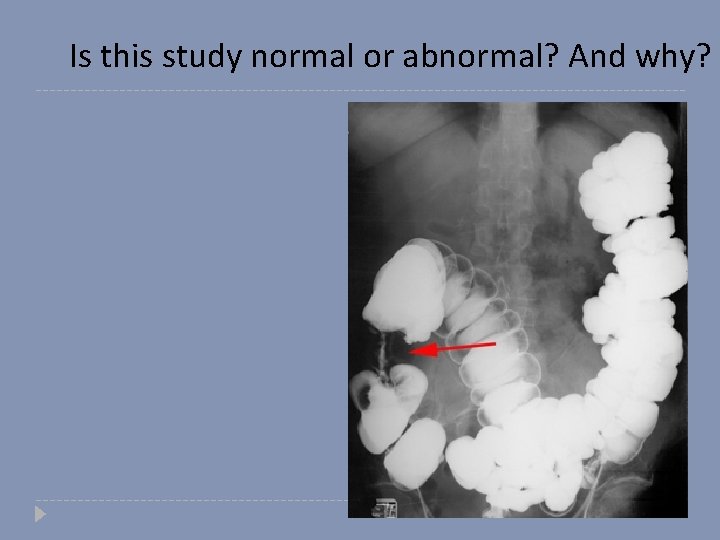

Is this study normal or abnormal? And why?

Abnormal study Colon Cancer (apple core sign)

Apple core sign